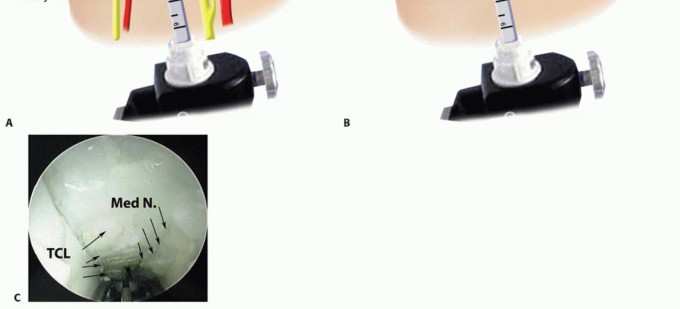

Endoscopic Carpal Tunnel Release (ECTR)

Endoscopic techniques, such as the single-portal Agee method, offer a minimally invasive alternative that preserves the overlying palmar skin and subcutaneous tissues, thereby accelerating early functional recovery.

A 1 to 1.5 cm transverse incision is made in the proximal wrist crease, positioned ulnar to the palmaris longus tendon. Dissection is carried down through the antebrachial fascia. A U-shaped flap of fascia is often elevated to create a secure entry portal. Serial dilation of the carpal canal is performed using blunt synovial elevators to clear the undersurface of the TCL and displace the median nerve radially and volarly, creating a safe optical cavity.

The endoscopic blade assembly is introduced into the canal, hugging the undersurface of the TCL. The surgeon must maintain strict spatial orientation, keeping the device aligned with the ring finger. The transverse fibers of the TCL must be clearly visualized across the entire width of the endoscopic monitor. If visualization is obscured by tenosynovium or if the anatomy is unclear, the procedure must be immediately converted to an open approach.

Once the distal edge of the ligament and the intervening fat pad are positively identified, the retrograde blade is deployed. The device is smoothly withdrawn proximally, sharply dividing the TCL under continuous direct visualization. A second pass with the endoscope is mandatory to confirm complete division of all ligamentous fibers. The portal is then closed with simple skin sutures.